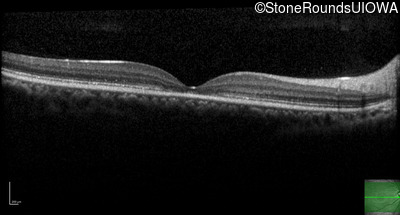

AR Stargardt Disease (IIA)

Age at visit:

16 years

OD

OS

20/125

AR Stargardt Disease

ABCA4

Val256Val GTG>GTT

Gly1961Glu GGA>GAA

AR